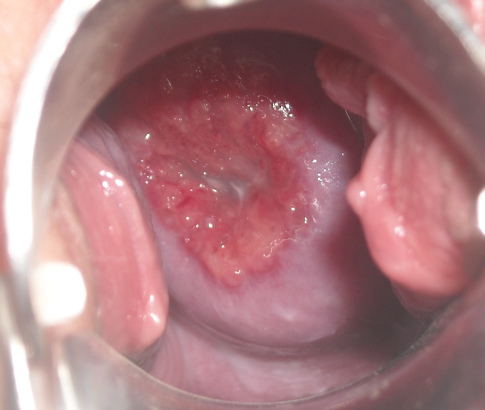

Ailsa, a 34 year old G3P3 woman, presents to your office with post-coital spotting of 6 months duration. She is otherwise healthy. Only medication is OCP.

Her last pap was 5 years ago. Smoker. Social EtOH.

On pelvic exam, you see the following:

What conditions are in your differential diagnosis? (Chose any)

• Ectropion

• Cervical dysplasia (LSIL/HSIL)

• Cervical Cancer

• Cervical polyp

• Cervicisitis/STI